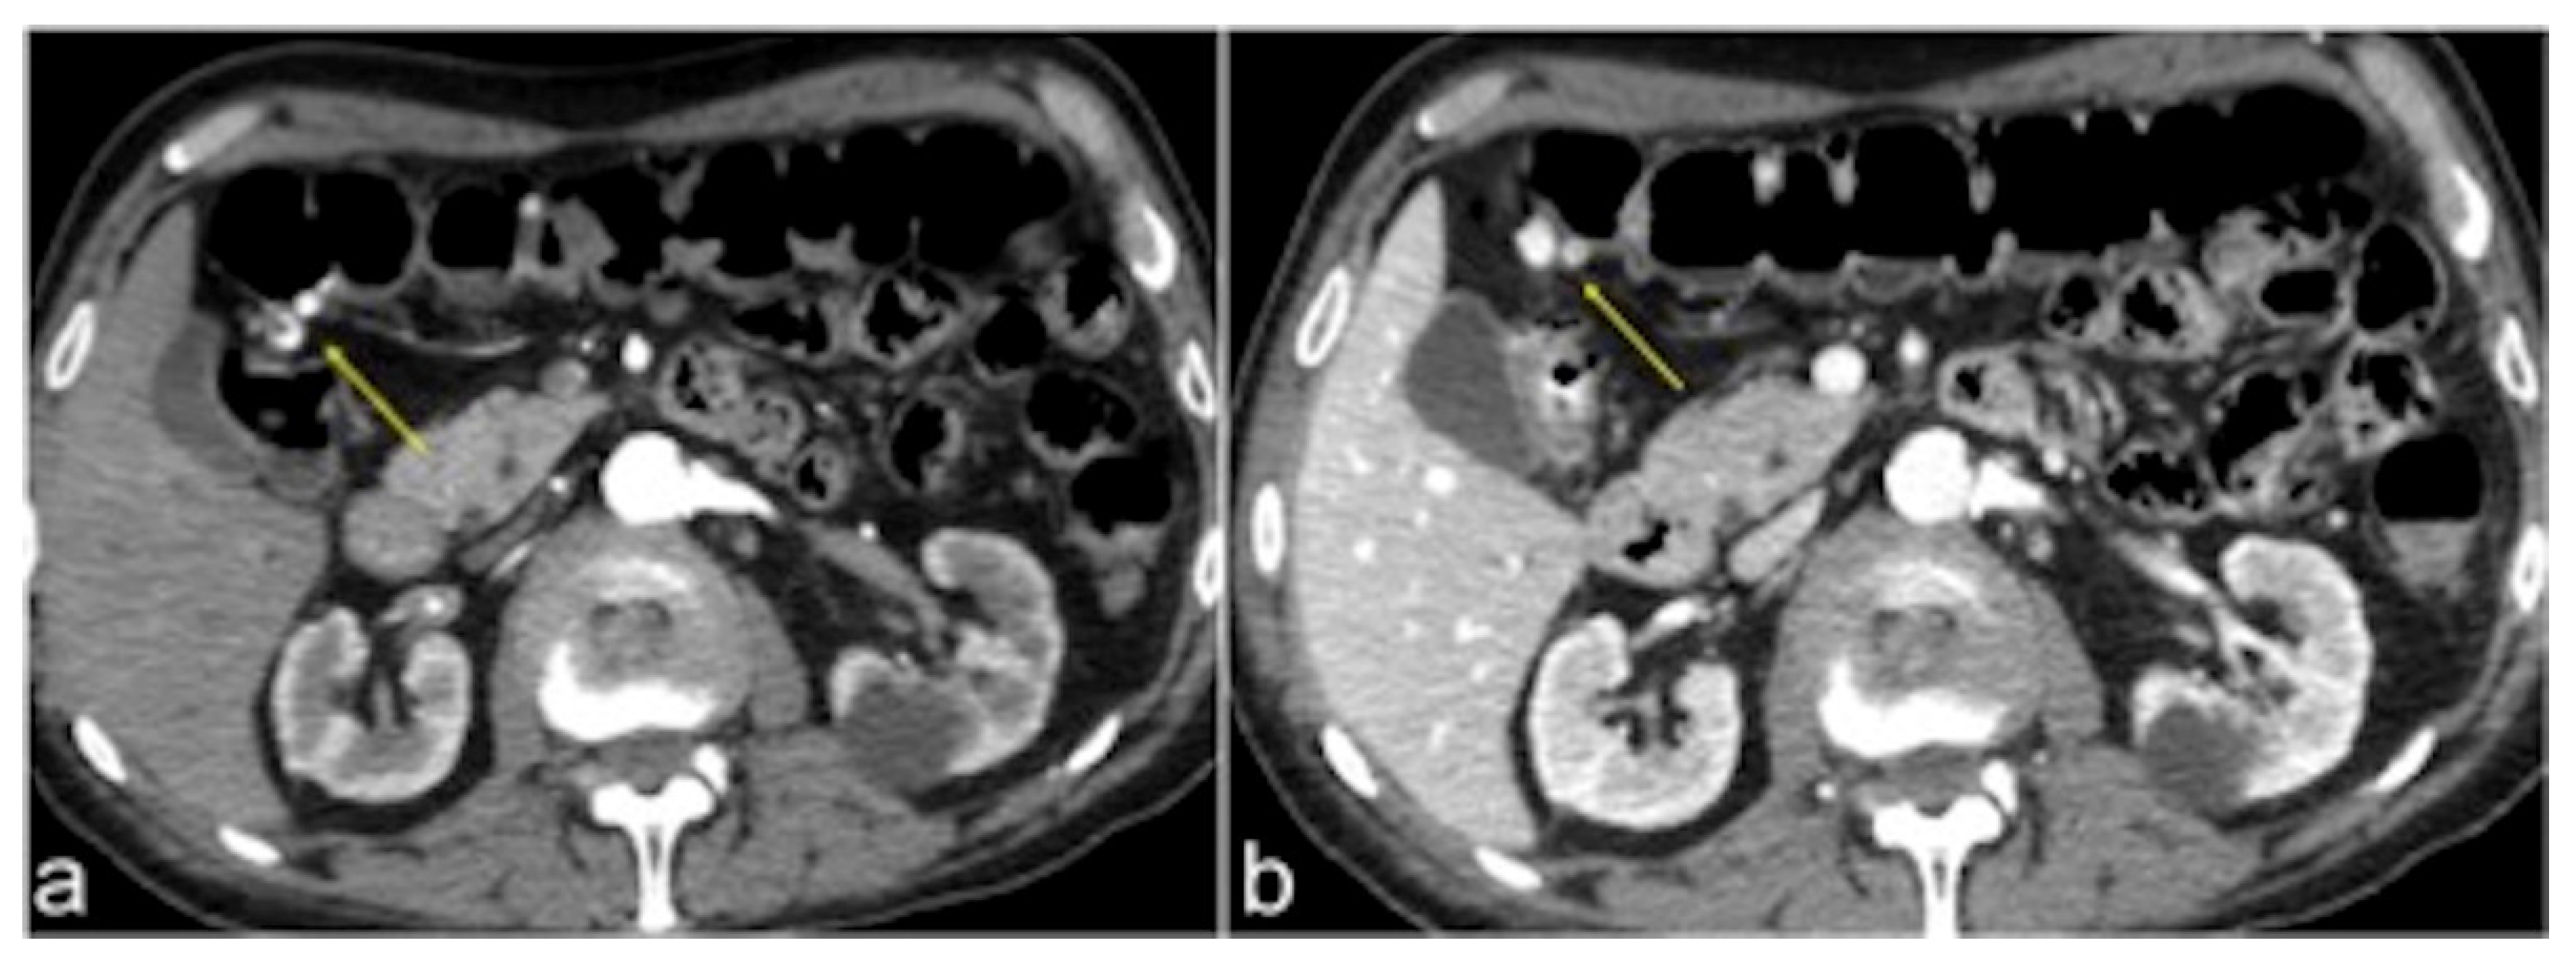

| Aorto-Enteric Fistula (Figure 31) | Bleeding in a patient with a history of surgery for aortic aneurysm. | A connection between the aorta and the intestinal lumen. Absence of adipose cleavage planes. |